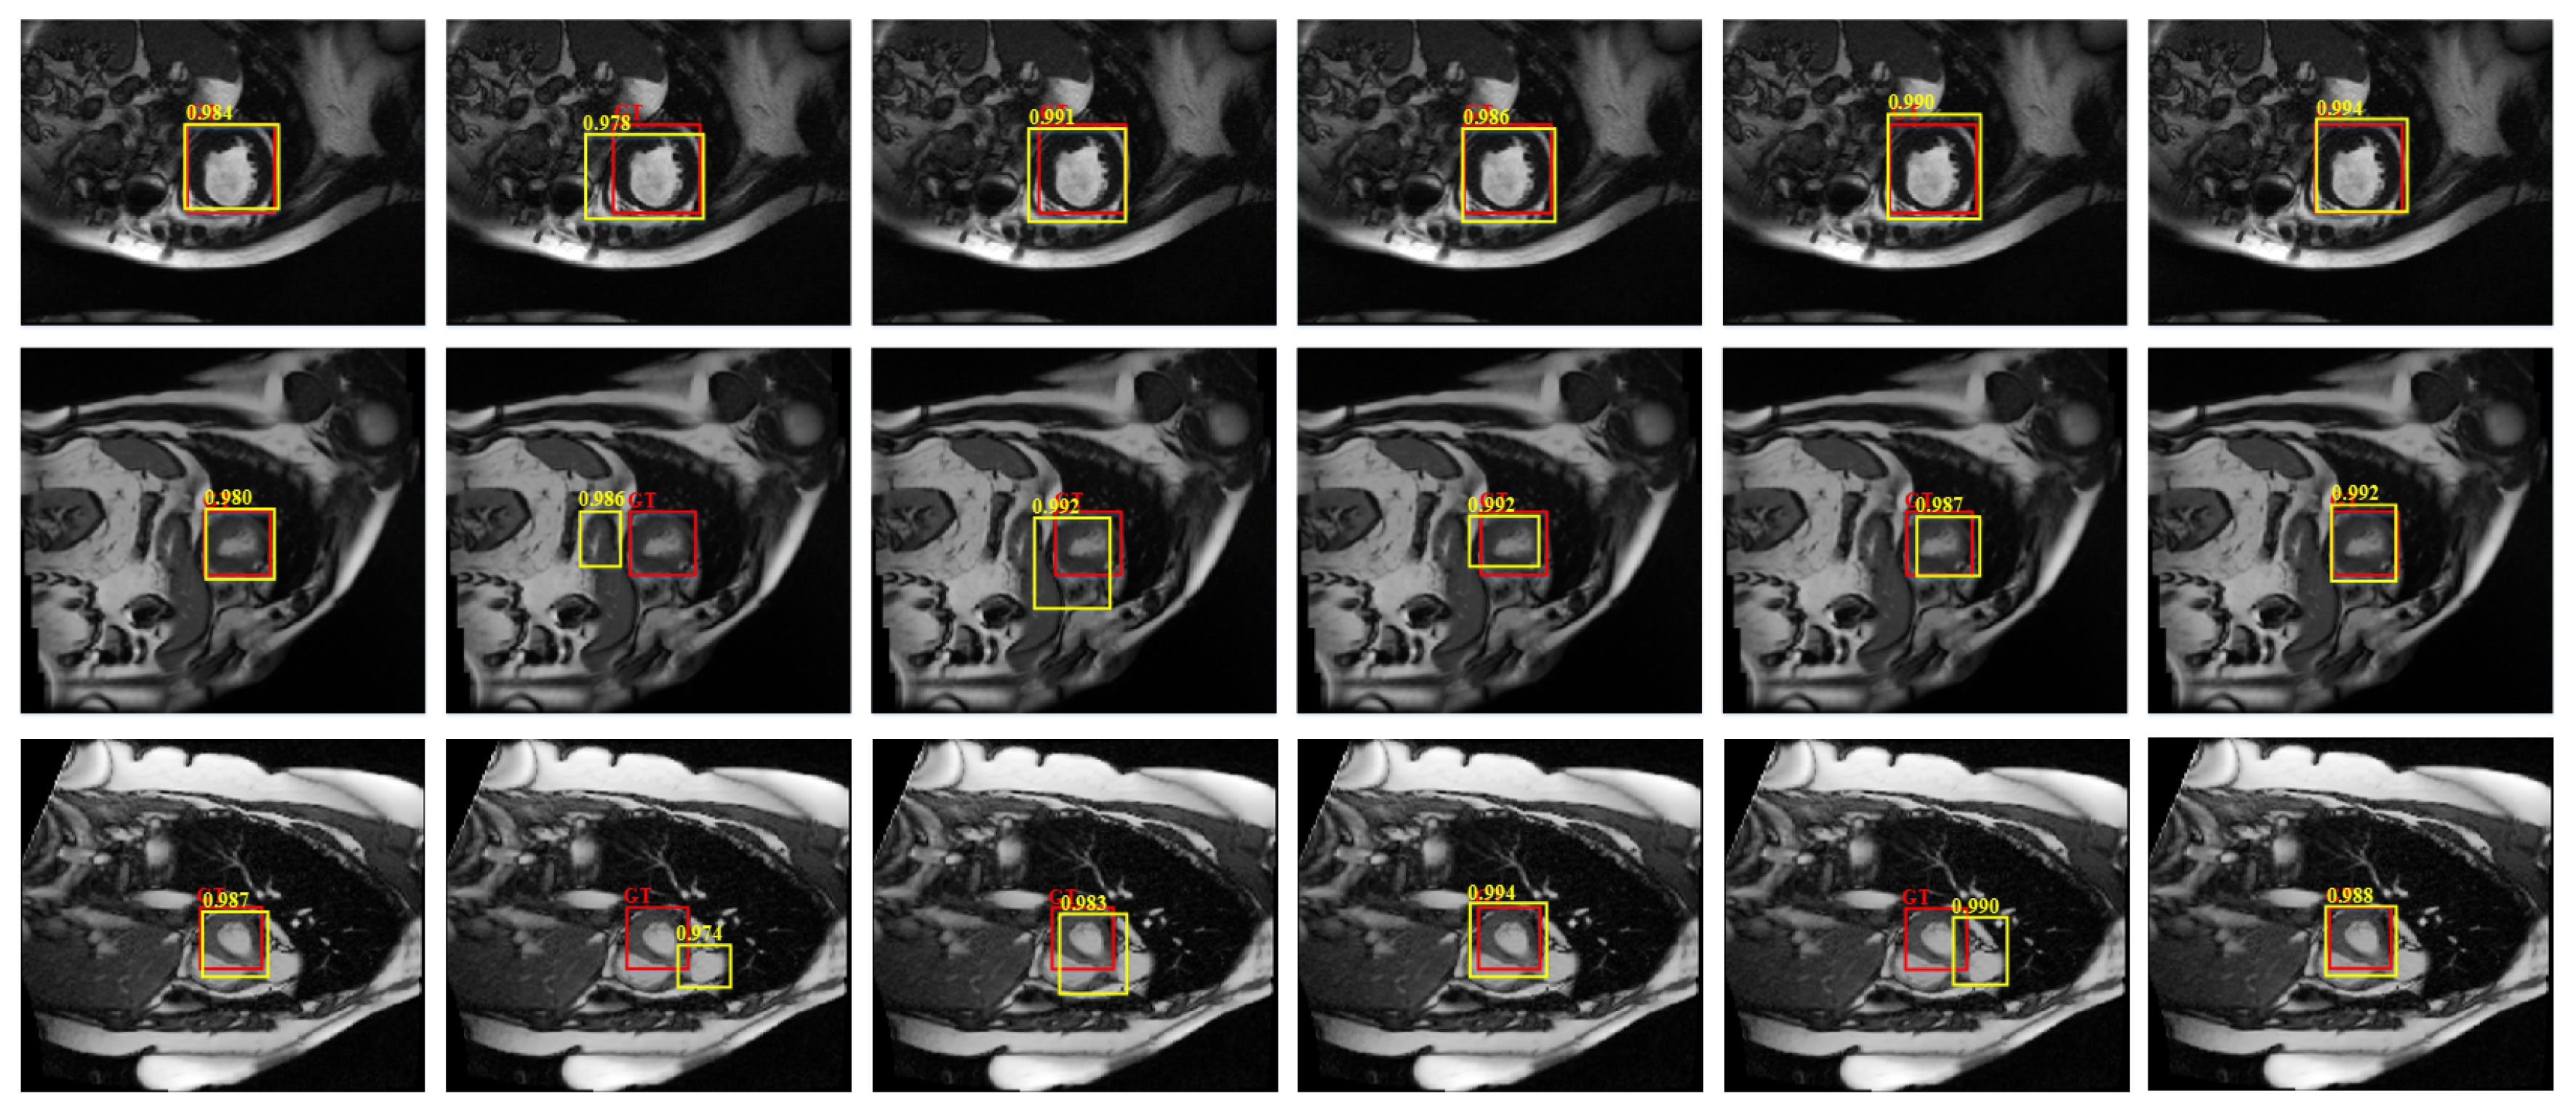

4.4.1. Detection Performance